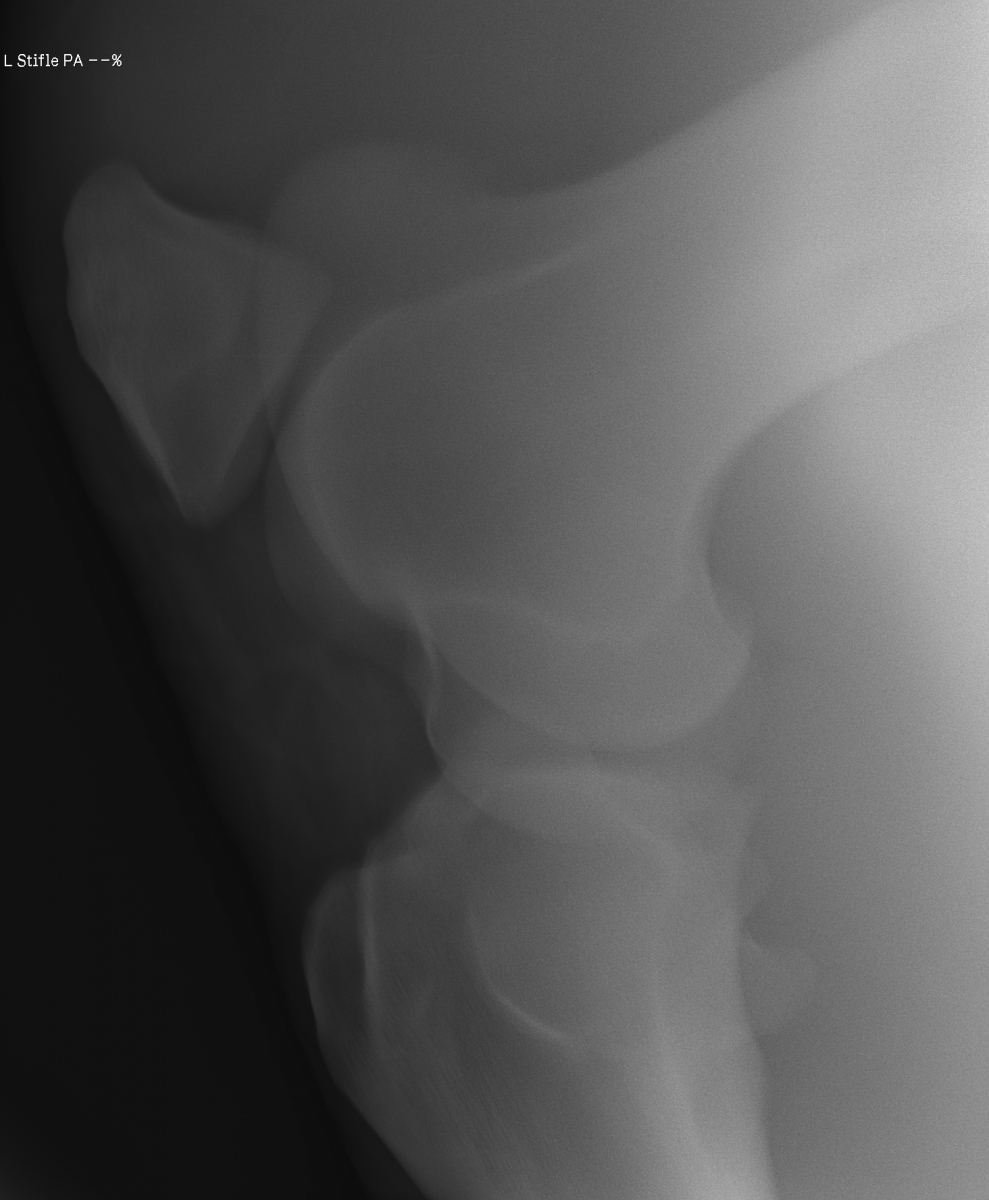

添付のレントゲン画像をご確認ください。現状渡しのノークレームノーリターンでお願いいたします。記載事項に関するキャンセルには応じられません。

前走で暴れた際にひねって、ヒビが入ってしまったのではないかと思われます。舎飼にて安静を保ち、時間を掛けて自然治癒を待つ他なく、早くても実戦復帰まで半年は要すでしょう。テンションのコントロール、ゲート枠内での駐立不良をなんとかしようと試行錯誤してアプローチしてみましたが、結果を出すことができませんでした。なお、興奮時にDDSP(軟口蓋背方変位)のような症状をみせることがあります。(船橋競馬・佐藤裕太調教師)

※2022年12月17日の競走にて左後脛骨不全骨折を発症しています(全治6~9ヵ月)。